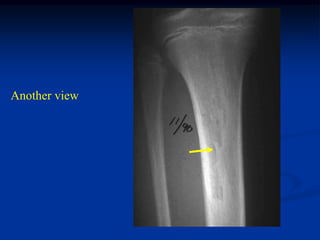

Case #592

11 year female

periosteal chondroma

proximal tibia

Another view